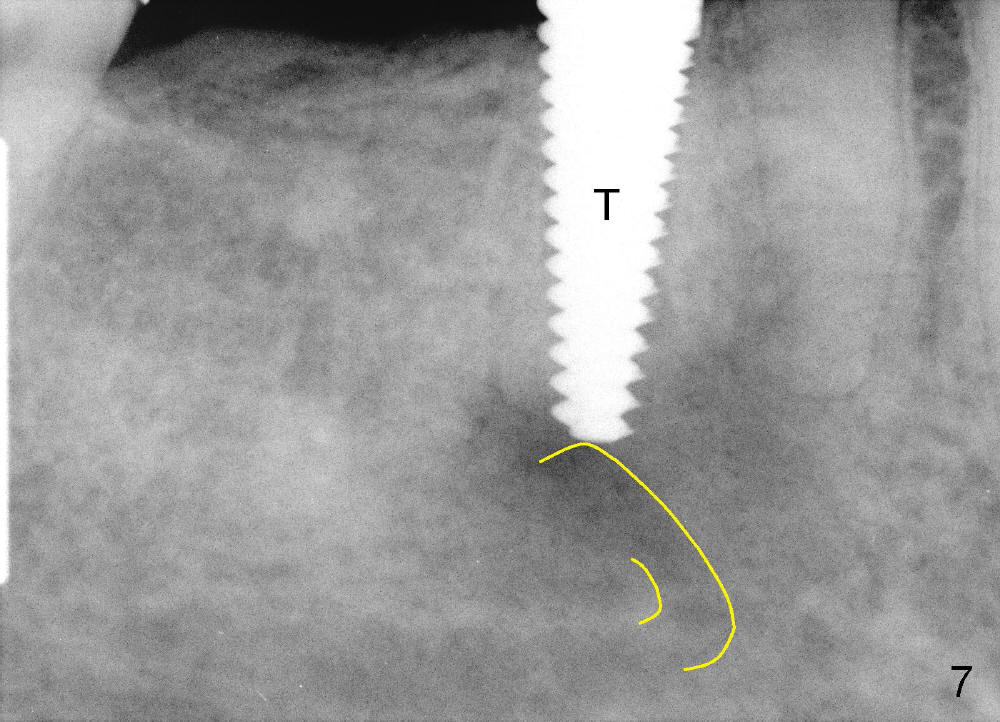

Osteotomy is created by using taps manually. There is no engagement of 5x20 mm tap (at the depth of 17 mm) with the socket. When a 6x20 tap (17 mm deep) is inserted, it is stable (Fig.7). In order to engage better, a 6x17 tapered drill is used (force applied lingually). Finally 6x17 mm implant (Fig.8 I) is inserted with torque more than 60 Ncm. The opening of the socket is obliterated by the large diameter implant, as evident by Fig.9,10 (2 weeks postop). There is no sign or symptom of paresthesia intra or post-op.